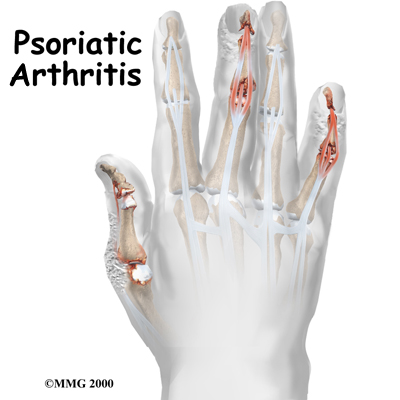

Psoriatic Arthritis

Psoriasis is a disease that most people think of as primarily a skin disease because the condition causes a persistent rash in various areas of the body. Psoriatic arthritis is a type of joint disease that occurs in roughly seven percent of people who have psoriasis. Psoriatic arthritis affects people of all ages, but most get it between the ages of 30 and 50. Usually a patient has psoriasis (the skin rash) for many years before the arthritis develops, and usually the arthritis comes on slowly, ...